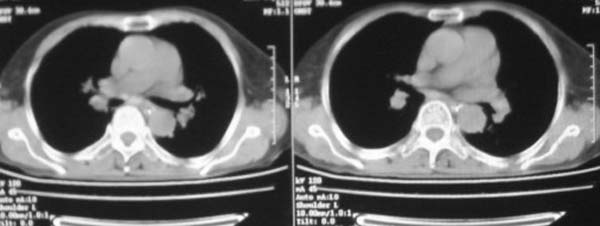

女,78岁,声嘶月余,否认有既往病史,有粉尘接触史10年。

颈部见多枚淋巴结肿大,考虑尘肺继发结核,喉部淋巴结钙化,不除外喉部慢性淋巴结炎、喉淀粉样变及类癌等

肺癌伴纵膈、双颈部淋巴结转移;尘肺。

右上肺癌伴肺内转移及纵隔淋巴转移 左上肺结核 图像有点模糊

双上肺结节融合影,周围有纤维条索影,结合粉尘接触史,首先考虑尘肺。双侧颈部有增大淋巴结,有声嘶表现,肺癌淋巴结转移不能排除。可结合颈部淋巴结活检。